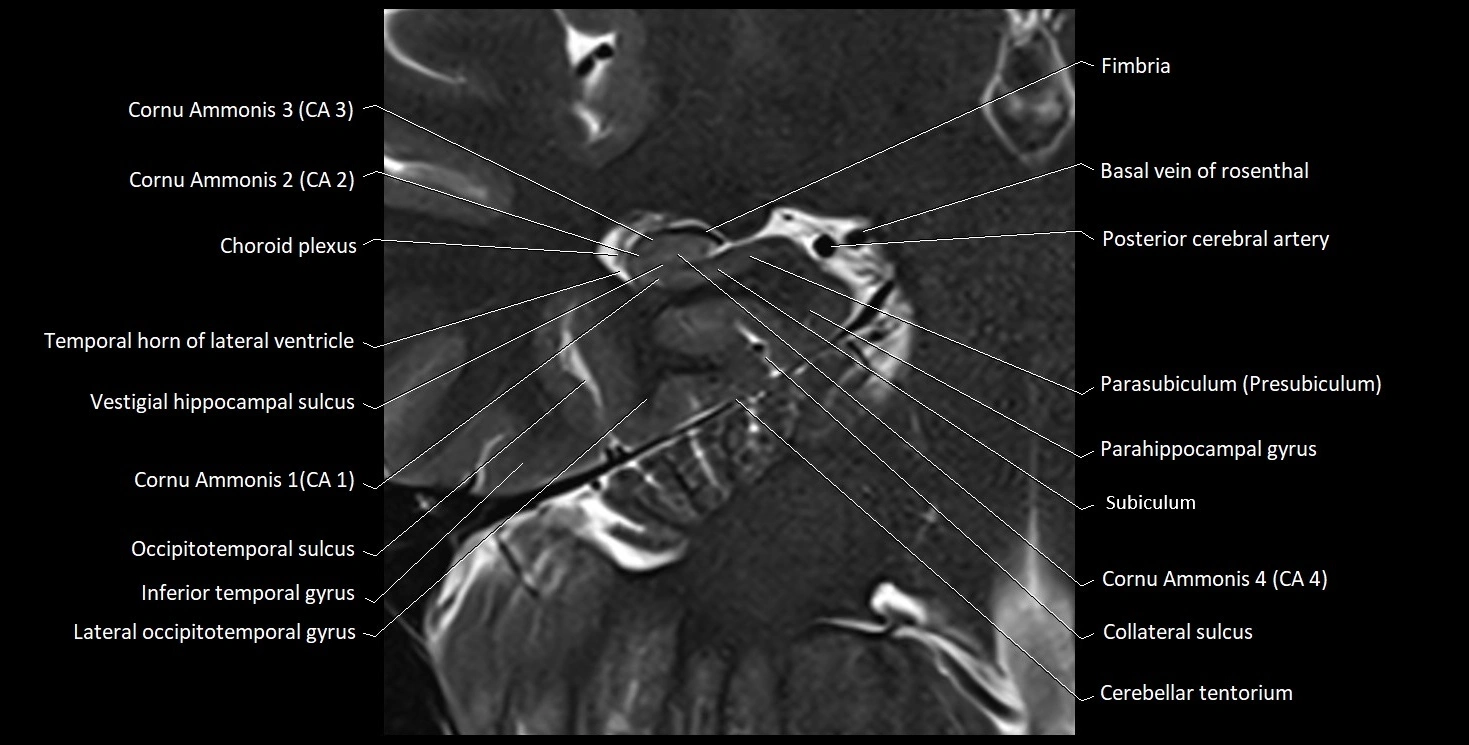

MRI images

image